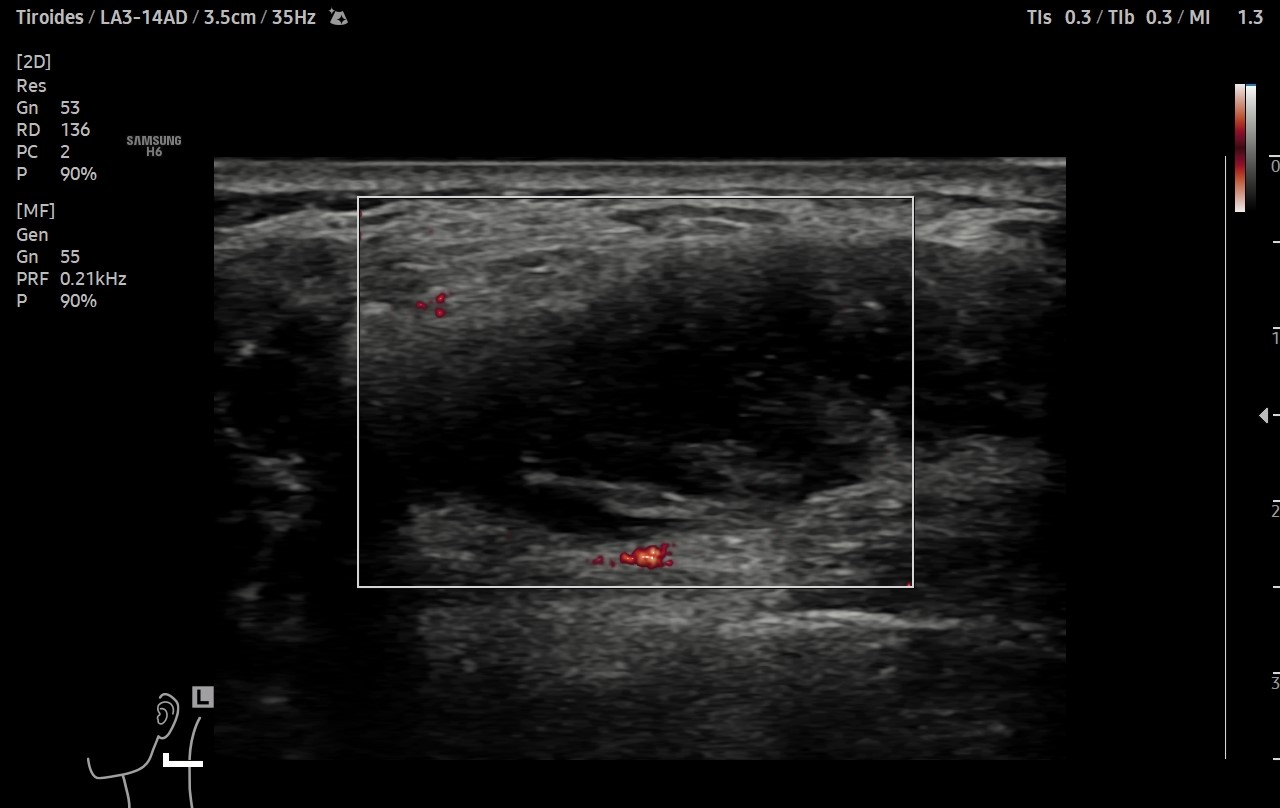

Ante sospecha clínica de malignidad se realiza ecografía.

Hallazgos ecográficos

Ecografía clínica de cuello: objetivando en cara lateral izquierda una imagen hipoecogénica, lobulada, heterogénea y vascularizada al Doppler, de aproximadamente de 3 cm, con apariencia de depender de la capa muscular. Adicionalmente, se detectó un nódulo tiroideo izquierdo con microcalcificaciones, aunque la TSH era normal.